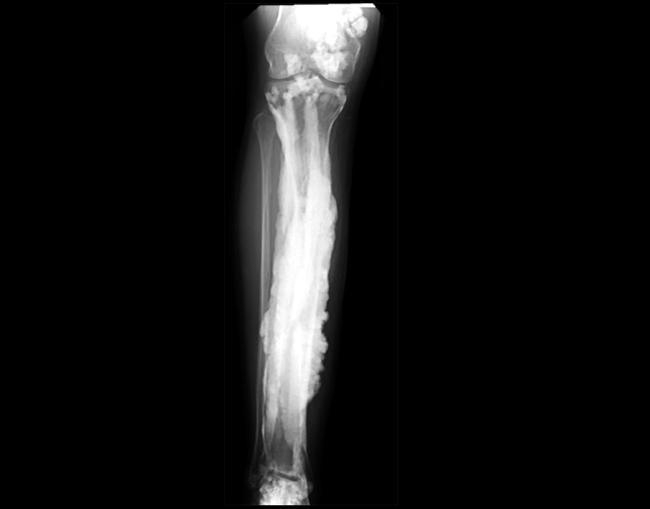

Researchers at the National Institutes of Health worked with 15 patients from around the world to uncover a genetic basis of “dripping candle wax” bone disease. The rare disorder, known as melorheostosis, causes excess bone formation that resembles dripping candle wax on x-rays. The results, appearing in Nature Communications, offer potential treatment targets for this rare disease, provide important clues about bone development, and may lead to insights about fracture healing and osteoporosis.